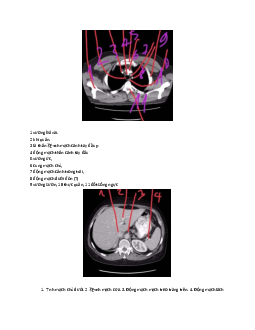

Tài liệu Giải phẫu cơ thể | Trường Đại học Kỹ thuật Y - Dược Đà Nẵng340 170 lượt tải 11 trangTài liệu Giải phẫu cơ thể | Trường Đại học Kỹ thuật Y - Dược Đà Nẵng. Tài liệu được biên soạn dưới dạng file PDF gồm 11 trang, giúp bạn tham khảo, ôn tập và đạt kết quả cao trong kì thi sắp tới. Mời bạn đọc đón xem! Danh mục: Đại học Kỹ thuật Y - Dược Đà NẵngMôn: Giải phẫu cơ thểDạng: Tài liệuTác giả: 48 Nguyễn Thị Anh Thơ1 năm trước